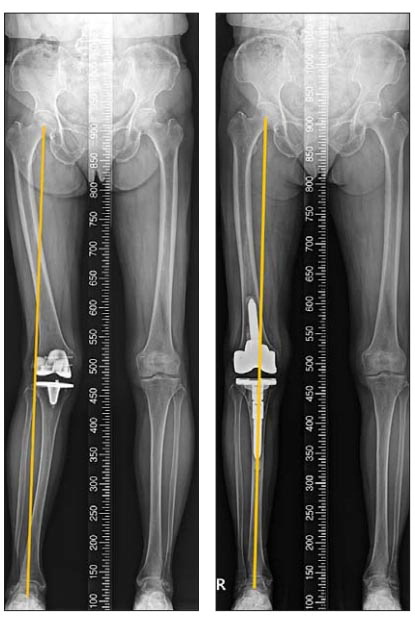

| ¼ö¼ú Àü¡¤ÈÄ ´Ù¸®Á¤·Ä ¸ð½À. |